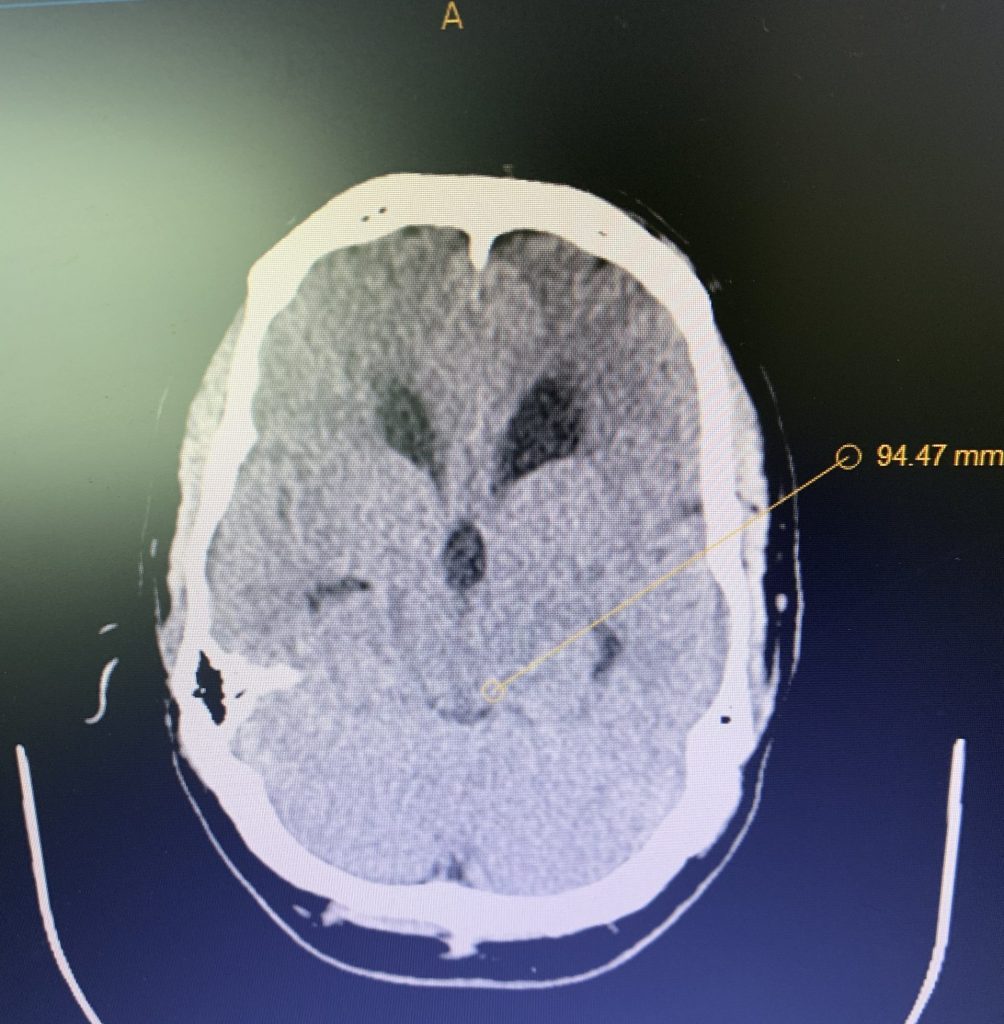

Hydrocephalus and Brainstem Tumor

Author: Jonathan L. Brisman M.D., F.A.C.S., Read More!